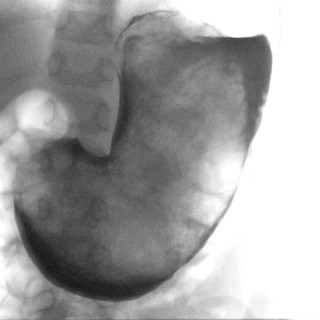

Adhesjon av de små kjønnsleppene er relativt vanlig (fig 1), i litteraturen er det anslått å forekomme hos 0,6 – 3,3 % av prepubertale jenter (1, 2). Leger bør derfor kjenne til tilstanden, som også er omtalt i Norsk Elektronisk Legehåndbok (3). I engelsk litteratur brukes begrep som «labial adhesion», «labial agglutination», «labial fusion» eller «synechia vulvae» (4). I Norge omtales tilstanden som labiale adhesjoner eller synekier, sammenliming, sammenvoksning, sammenlodding eller agglutinasjon av de små kjønnsleppene. Siden leger sjelden undersøker jenters underliv, vil tilstanden ofte gå...